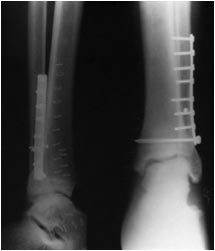

Вопрос не очень понятно сформулирован. Что не так? Поставлен обычный

кортикальный не блокированный в пластине винт. Во вложении - фото

отрывка из руководства по внутреннему остеосинтезу АО. В переводе А.В.

Королева. Как раз там рекомендуется введение обычного 3.5 мм шурупа

через оба кортикальных слоя большеберцовой кости.

> Этот винт проведен через сам синдесмоз на 1 см проксимальнее сустава - а это в соответствии с какими рекомендациями?

Во вложении рентгенограмма из руководства Кэмпбэлла, издания 2013 г.

(стр. 2623), демонстрирующая технику фиксации синдесмоза через отверстие

в пластине. Расстояние от суставной линии там явно не 2 см. тем более не 3.